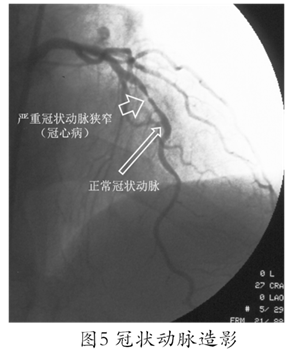

需要强调的是:对于绝大多数怀疑冠心病的患者来说经导管冠状动脉造影是目前诊断冠心病的“金标准”,它不仅可以直观而清晰地反映冠状动脉病变的几何学特征(图5)、也可间接地部分反映冠状动脉的功能状态(尤其是血流动力学特征)而且创伤小、副作用少、安全性较高,更重要的是冠状动脉造影结果也是对于确诊为冠心病的患者如何进行治疗决策的重要依据(冠状动脉造影可以明确冠状动脉病变的范围和程度,进而决定是单纯药物治疗即可、还是需要植入支架或接受冠状动脉搭桥手术)!无论在欧美等发达国家和地区还是在中国,冠状动脉造影这一成熟的诊断技术已经成为临床诊断冠心病、指导冠心病治疗策略、判断冠心病患者预后的一项常规技术,因此,如果医生认为有适应症,患者对于冠状动脉造影不必有太多顾虑。如果医生经过分析、判断认为患者有进行冠状动脉造影检查的明确指证而没有及时进行,则可能延误诊断和治疗。